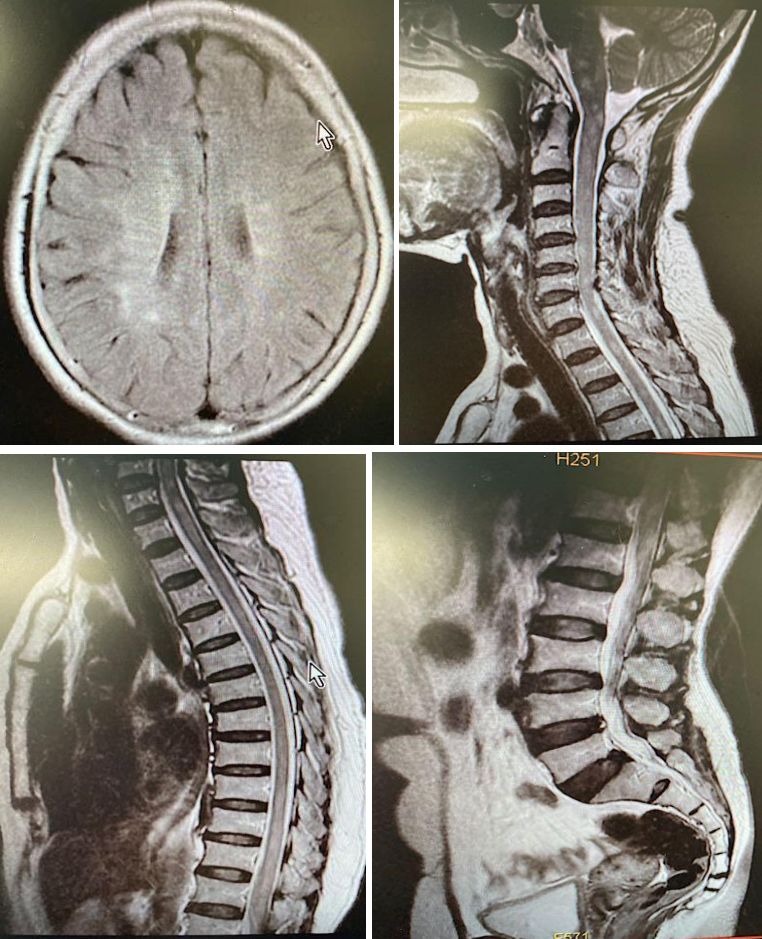

女,51岁,双下肢麻木、行走欠稳1月余,肌力5-级,双上肢正常,大小便障碍。

脑脊液化验结果如下:

答案:抗Hu抗体相关副肿瘤综合征。补充检查:抗Hu抗体阳性,胸部CT可见一个小结节存在,余无异常。中年女性患者,亚急性起病,双下肢麻木、行走不稳,肌力有减退,二便障碍。影像学见双侧半卵圆中心、脑干及脊髓长节段病变。结合病史、查体及影像考虑脱髓鞘、免疫及肿瘤代谢性疾病。患者CSF白细胞280,一般实验室检查无异常排除感染。好多老师看到了脑室旁髓静脉样条纹,考虑为自身免疫性GFAP星形细胞病。该病早期称为慢性或亚急性激素反应性非血管炎性自身免疫炎症性脑膜脑炎。病程也有类似,通常40岁女性以上易发,急性或亚急性起病,呈进行性加重或复发-缓解病程,临床表现多样,包括发热头痛,脑病,脊髓炎,视力异常,锥体外系症状,共济失调,自主神经功能障碍等。但是该病CSF检查白细胞数增多,蛋白升高,寡克隆区带阳性。脑脊液和血清中检测到GFAP抗体可确诊。影像特征性表现为垂直于脑室的脑白质血管周围线样放射状增强。

还有多数老师考虑脱髓鞘病,CSF蛋白较高,余正常,影像表现也不符合脱髓鞘病的特点,亦排除脱髓鞘疾病。对于脊髓病变,诊断思路如下:

➢ 观察病变节段的长短:长节段提示NMO、播散性脊髓炎或缺血;短节段常见于MS(通常<2个节段)。

➢ 观察横断面上病变的范围:部分受累提示MS;完全受累见横贯性脊髓炎。

➢ 观察横断面上脊髓受累的位置:后部提示MS,WitB12缺乏症;MS病灶常为圆形或扇形,多位于脊髓侧部或后部;前部病变可能是动脉性梗死及MS。

➢ 观察脊髓是否肿胀:横贯性脊髓炎或肿瘤,肿胀明显;若是MS或急性

播散性脊髓炎,脊髓不肿胀或轻微肿胀。

➢ 观察病变是否强化:多种病变可强化,星形细胞瘤也可以;脱髓鞘病变应与星形细胞瘤鉴别,尤其是出现脊髓肿胀,强化及患者症状进展缓慢时。其他常见的脊髓肿瘤如室管膜瘤与血管母不难鉴别;转移瘤少见。